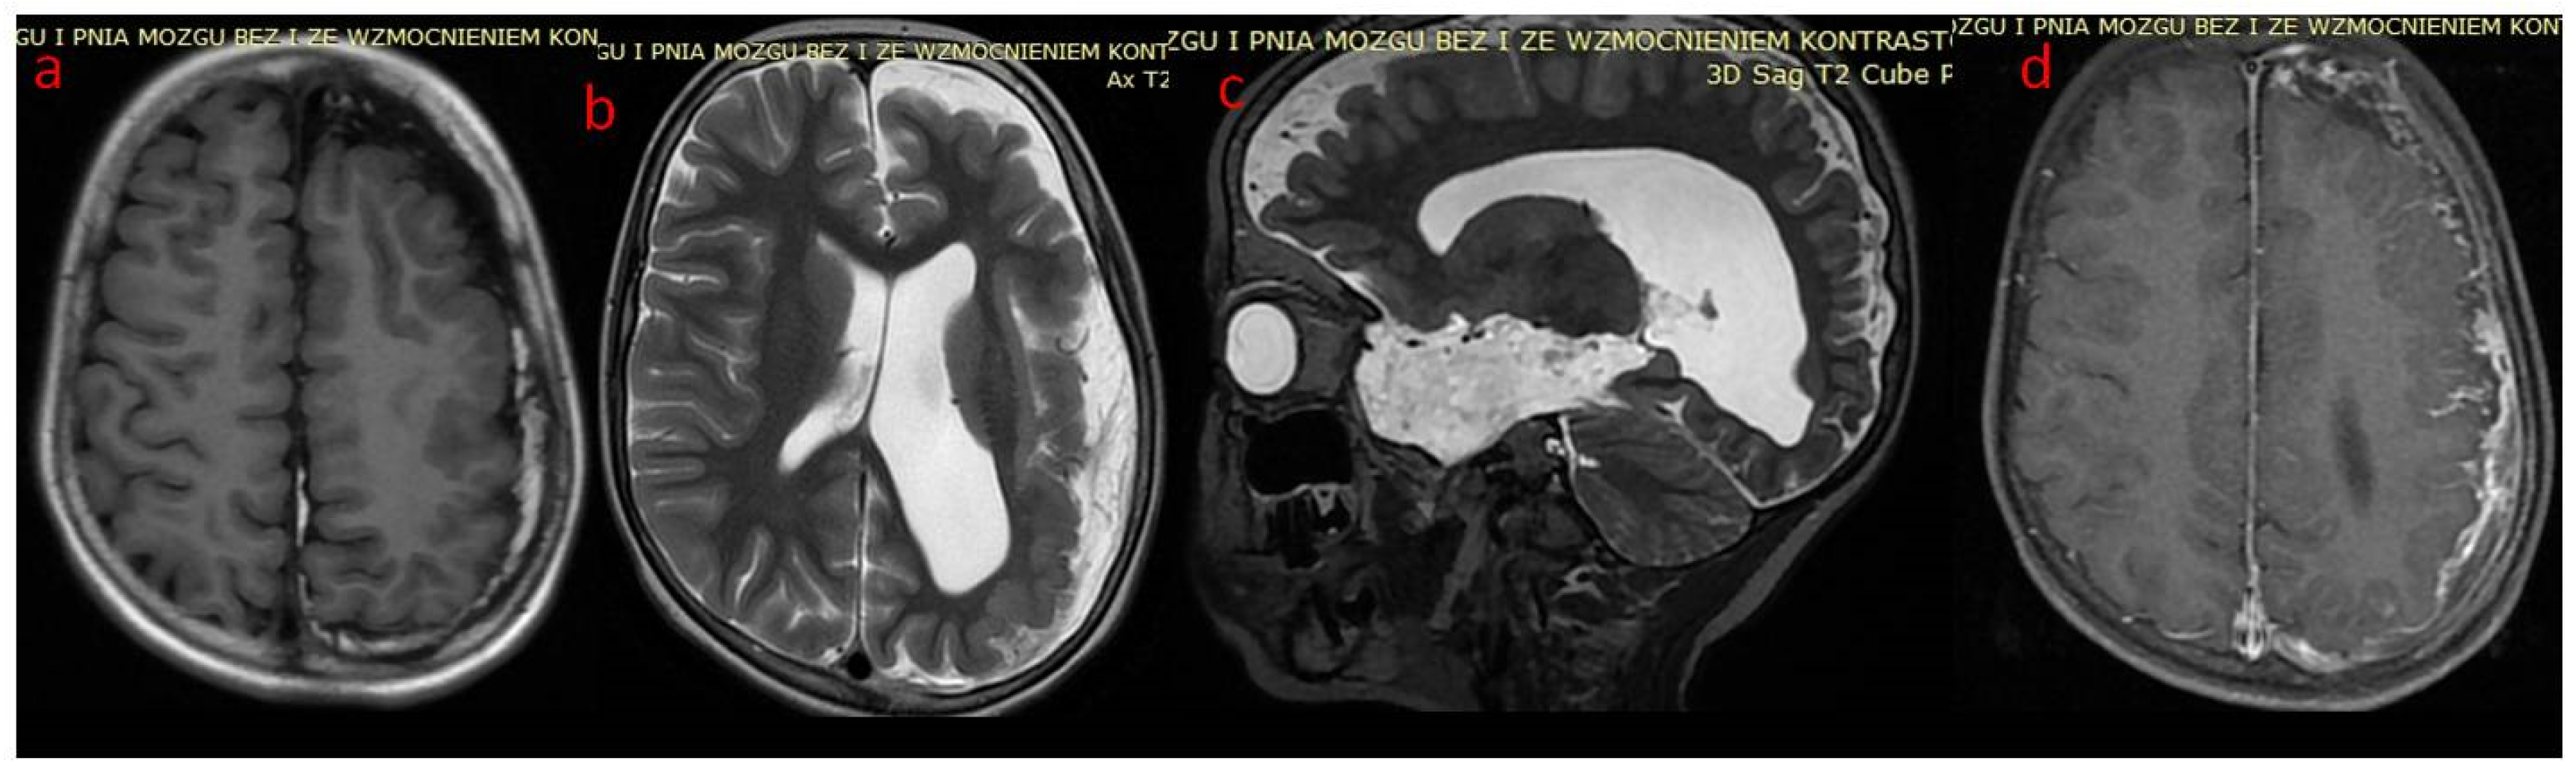

A novel Notch 3 mutation (pathogenic variant c.1565G>C) in CADASIL

A novel Notch 3 mutation (pathogenic variant c.1565G>C) in CADASIL Brain Mri Dental Crowns Clinical studies showing the severity of artifacts which dental materials are capable of causing in mri of head and neck,. Dental materials have important implications on the use of mri as a diagnostic imaging modality. A case of a dislodged crown. In some cases, it may be advisable to remove a crown and replace it with porcelain or resin before. Brain Mri Dental Crowns.